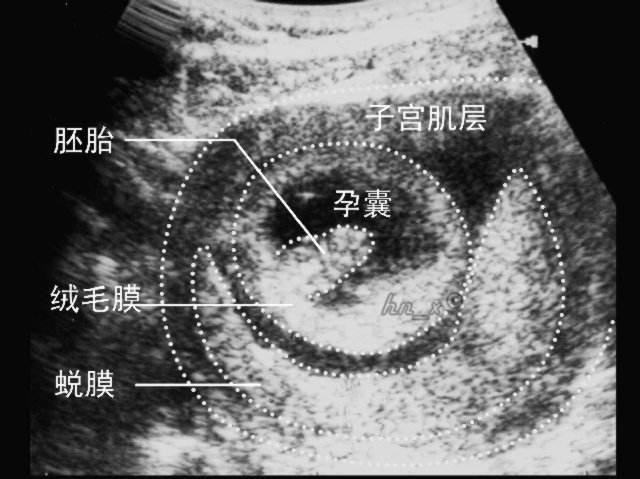

这个阶段,医生会重点看 孕囊(一般是在孕30-40天孕囊出现),医生会根据“孕囊的大小、位置、性状”等,来判断胚胎是否在正常发育。

① 孕囊大小

这里说的“孕囊大小”,指的是孕囊的直径,在怀孕6周时孕囊的直径约为2cm。

② 孕囊形状和位置

不少人,在怀孕早期会根据孕囊的性状来判断怀的男孩还是女孩,其实这是没科学道理的,不过在这个阶段,的确可以通过B超看孕囊的性状是“椭圆形还是圆形”,而医生会根据孕囊的性状、位置等判断胎儿的发育情况。